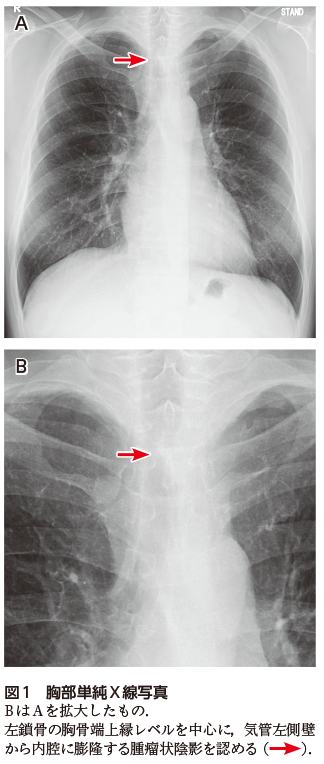

中皮腫瘍取扱い規約第2版が発行されました。【裁断済み】カプラン臨床精神医学テキスト 日本語第3版。 - 日本石綿・中皮腫学会, 解答・解説】労作時の息切れを主訴に受診した40歳代男性|実践,